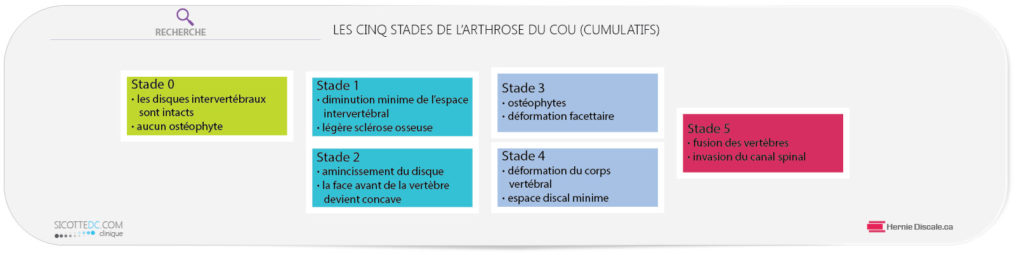

STADE 0

À ce stade, tous les disques intervertébraux sont intacts. La face arrière de la vertèbre (stade 0 (a) ne présente aucun ostéophyte (ces petits bouts d’os dont nous avons parlé plus haut). L’espace intervertébral (b) est épais et intact. Si l’on traçait un carré imaginaire, toutes les vertèbres pourraient s’y insérer (c).

STADE 1

La diminution de l’espace intervertébral est minime, mais présente (d). Un oeil non habitué pourrait difficilement faire la différence. Lentement, la face avant de la vertèbre commence à s’éroder (e). Ceci est souvent dû à la perte de courbure cervicale. Cette perte augmente le poids sur la face avant de la vertèbre (stade 1 (b), produisant ainsi des becs de corbeau (ostéophytes). L’apparition même minime de ces ostéophytes devient évidente (f).

STADE 2

L’amincissement du disque se visualise bien (g). Les ostéophytes sur la face arrière sont d’avantage visibles à cause de cette augmentation de la blancheur de l’os (h). L’os se situe dans une zone de pression croissante. La face avant de la vertèbre devient concave (i). La vertèbre ne pourrait plus s’insérer parfaitement dans un carré…

STADE 3

L’engorgement du canal vertébral par des ostéophytes sur les faces arrières des vertèbres est commun (j). La face de la vertèbre se trouve soumise à un stress anormal, ce qui est démontré par l’apparition d’une certaine blancheur juste au-dessus du disque (k). Le ligament longitudinal antérieur montre parfois des signes de calcification (I), ce qui limite le mouvement normal du cou vers l’arrière.

STADE 4

Une subluxation (déplacement mineur) significative de la vertèbre (m) apparaît. L’espace intervertébral est presque inexistant et la face de la vertèbre est déformée (n).

STADE 5

À ce stade, la fusion, est inévitable (o) et elle peut se produire à plusieurs niveaux vertébraux. La description des stades que nous venons de faire est utilisée à notre clinique lors du rapport des conclusions à la suite de votre examen. La dégénérescence est un mal permanent lorsqu’elle a débuté. Elle ne peut pas être éliminée complètement.